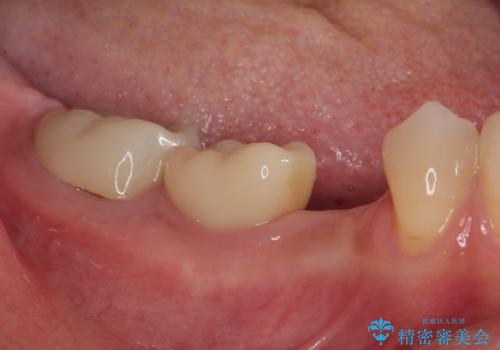

他にも銀歯や欠損となっている歯に対しての治療も希望されたため、補綴治療を行うこととしました。

インプラント治療をきっかけに、銀歯を全てセラミックに替えていきました。